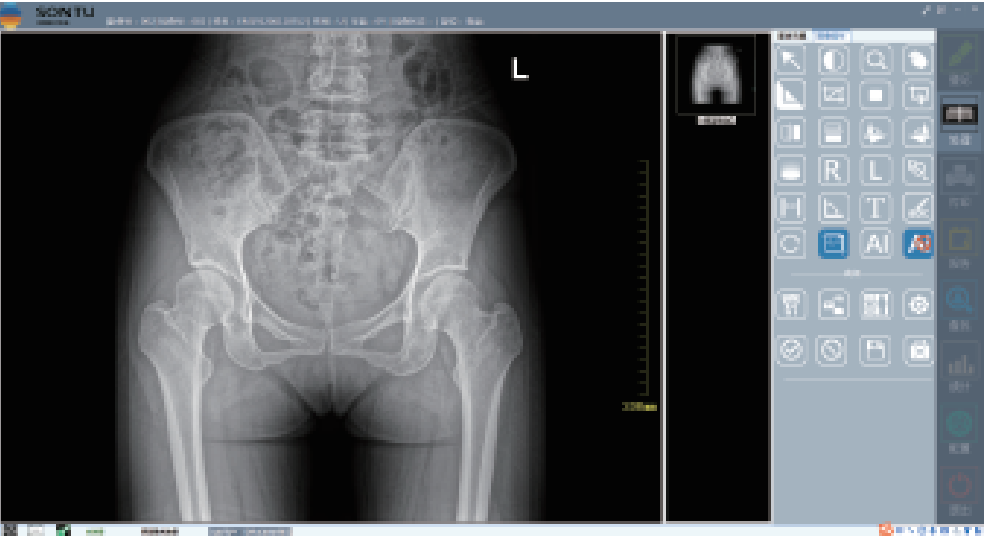

-

图像采集

-

图像操作

- 02

数字化透视:

为全身各部位透视、透视下定位、透视下穿刺及透视下数字点片摄影

- 03

数字化摄影:

为全身各部位摄影,包括常规立位、卧位摄影等(如胸片、颈椎、腰椎、腹部等)和特殊倾斜、角度摄影(如髌骨轴位、跟骨轴位等)

- 04

深图软件操作系统:

一键即可完成辅助诊断,定位可疑病变

- 05

深图AI辅助诊断系统标注示意:

标注异常位置、呈现病变信息